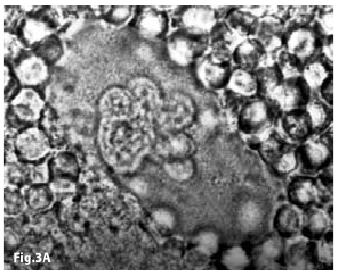

Figure3A